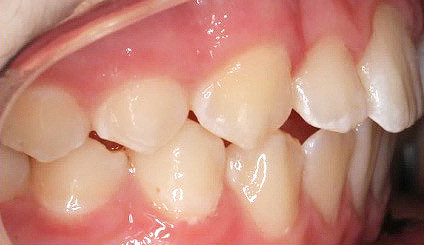

Klinisches Fallbeispiel 2 (Abb. 2a–y)

Distalbiss und tiefer Biss bei einem zwölfjährigen Mädchen. Die Behandlung erfolgte mit Invisalign und Precision Wings. Insgesamt waren zwei Schienensätze notwendig. Die Gesamtbehandlung dauerte 18 Monate.Bei der Planung des ClinCheck wurde der tiefe Biss vorwiegend über eine Intrusion der Unterkieferfront behoben, um die Lachlinie der Patientin nicht negativ zu beeinflussen. Die Oberkieferfront wurde nur retrudiert, jedoch vertikal nicht intrudiert. Während der Phase des Mandibular Advancement wurde die Wirkung der Precision Wings durch den Einsatz von Klasse II-Gummizügen unterstützt. Schlussendlich wurde auch der hängenden Okklusionsebene durch eine einseitige Intrusion der Molaren im ersten Quadranten Rechnung getragen.